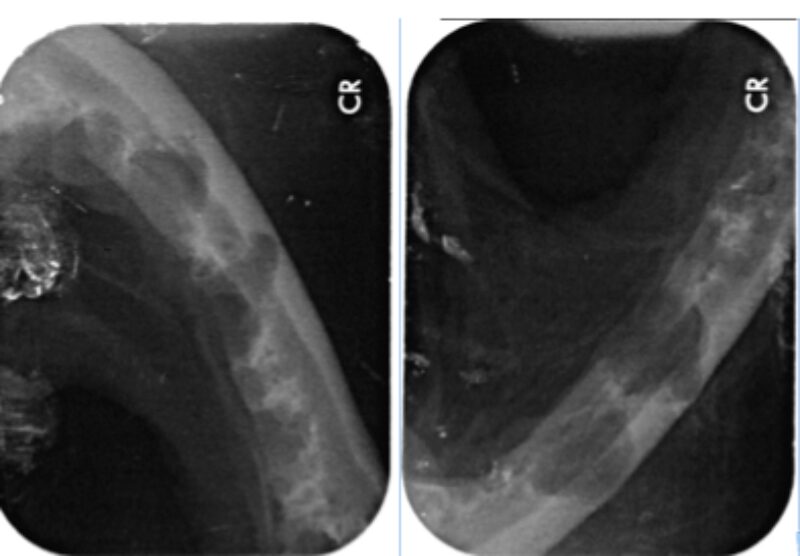

In Narkose sah man auf Leilas Röntgenbildern dann das gesamte Ausmaß ihrer Zahnerkrankung. Bis auf die Canini wiesen alle Zähne hochgradige Wurzelentzündungen mit Osteolysen des Kieferknochens auf. Deshalb konnte man auch schon von außen die Zahnhälse freiliegend sehen. Im Wurzelbereich waren die Veränderungen so schlimm, dass der Unterkiefer kurz vor einer Fraktur stand.

Solche Veränderungen treten oft bei einer hochgradigen Parodontitis auf. Eine Parodontitis ist die Entzündung des gesamten Zahnhalteapparates (also des Kieferknochens, des Zements, der Paradontalfasern und des Zahnfleischs) und wird durch die Bakterien, welche im Plaque enthalten sind, hervorgerufen. Diese zerstören die Anheftung der Gingiva am Zahn, und die Bakterien können bis zur Wurzel vordringen. Hier rufen sie Entzündungsreaktionen des Kieferknochens und der Gingiva hervor, wodurch beide sich zurückziehen und tiefe Paradontaltaschen entstehen lassen. Doch Leila hatte, wie auf den Bildern schön zu sehen ist, kaum Zahnstein oder Plaque.

Es ist sehr wichtig zu verstehen, dass eine Zahnreinigung ohne Aufnahme eines kompletten Zahnstatus inklusive Zahnröntgen nichts weiter ist als eine kosmetische Behandlung, da krankhafte Prozesse übersehen werden (abb. 7-10).